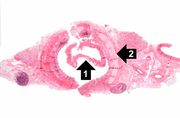

| 04:03, 21 August 2013 | IPLab10Candidiasis3.jpg (file) | 25 KB | This is a low-power photomicrograph of lymph node with three prominent areas of Candida colonies (arrows). Even at this low magnification, the purple-staining yeast and pseudohyphae can be easily seen. This section was stained with Periodic Acid-Schiff... | 1 | |